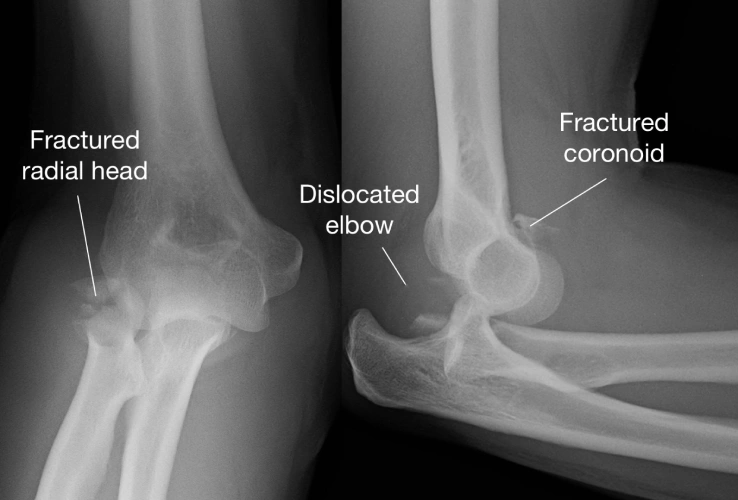

- Radial Head Fracture – break in the top of the radius near the elbow joint.

- Coronoid Fracture – less common, involving a small part of the ulna that stabilizes the joint.

- X-rays to confirm the type and severity of fracture